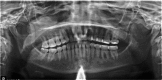

A 30-year-old woman presented for orthodontic treatment, with a chief symptom of a 'shifting bite' and concurrent facial asymmetry with aesthetic concerns. The patient had previously received treatment from several general dentists and several specialists, without accurate diagnosis. Radiological investigation coupled with biopsy confirmed a diagnosis of fibrous dysplasia. Proper diagnosis led to changes in the treatment plan and gave the patient realistic expectations about the options she had for the outcome of treatment. Prompt diagnosis by dental practitioners is critical to patient satisfaction and successful outcome; therefore, it is important to familiarise ourselves with the signs, symptoms and proper course of management of fibrous dysplasia.